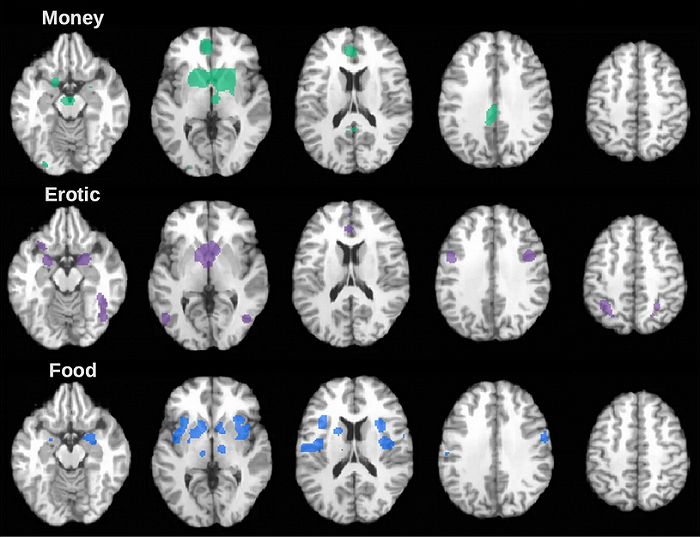

В результате ученые разработали модель системы вознаграждения, которая отражает, как активность мозга зависит от типов награды. Согласно ней, во всех трех случаях, но с разной интенсивностью и в разных полушариях, активируются базальные ганглии, в том числе хвостатое ядро, скорлупа и бледный шар. Поэтому исследователи предполагают, что именно базальные ганглии — ключевая структура системы вознаграждения, но роль каждого из ядер еще предстоит уточнить.

Кроме базальных ганглиев, включались и другие структуры,но их активация уже зависела от того, какую именно награду получали испытуемые. Так, при получении пищи и просмотре эротики активировался левый таламус, а при денежном вознаграждении — правый.

Вкусная еда активировала правый островок — он объединяет информацию, получаемую от эмоций, размышлений и ощущений внутренних органов, — и ограду. Ее связывают с сознательным восприятием — когда испытуемых просили дать оценку вкусу пищи, это требовало от них анализа и размышлений о своих ощущениях.

Эротические картинки и видео заставляли работать веретенообразную извилину. Она отвечает за воображение, в первую очередь визуальное. Вероятно, эротика включает фантазию, чего не происходит при получении награды в виде еды или денег. Также эротические картинки активируют амигдалу, ответственную за присвоение эмоциональной ценности различным стимулам.

Наконец, денежные вознаграждения помимо структур лимбической системы вовлекают лобные области неокортекса — зоны, наиболее развитые у людей. В отличие от биологических наград в виде еды и секса деньги также активируют прилежащее ядро. Прилежащее ядро когда-то называлось центром удовольствия, сейчас ему присваивают функции обучения и развития зависимости.

Также ученые подтвердили, что межполушарная асимметрия для разных наград действительно существует. В ответ на пищевую награду активируются в основном ядра, расположенные в правом полушарии мозга, на эротическую — правый наружный бледный шар и левое хвостатое тело, и на денежную — все ядра базальных ганглиев в обоих полушариях, включая прилежащее ядро.